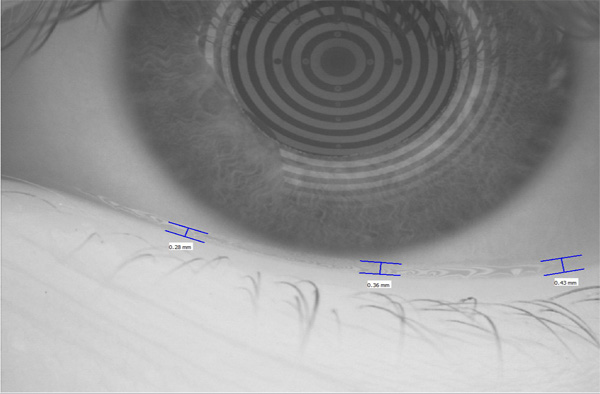

Trockenes Auge

Der Aufbau des Tränenfilms ist entscheidend für gutes Sehen. Wir analysieren Ihren Tränenfilm und geben Ihnen Handlungsempfehlungen, wie Sie am besten mit dem Problem "trockene Augen" umgehen.